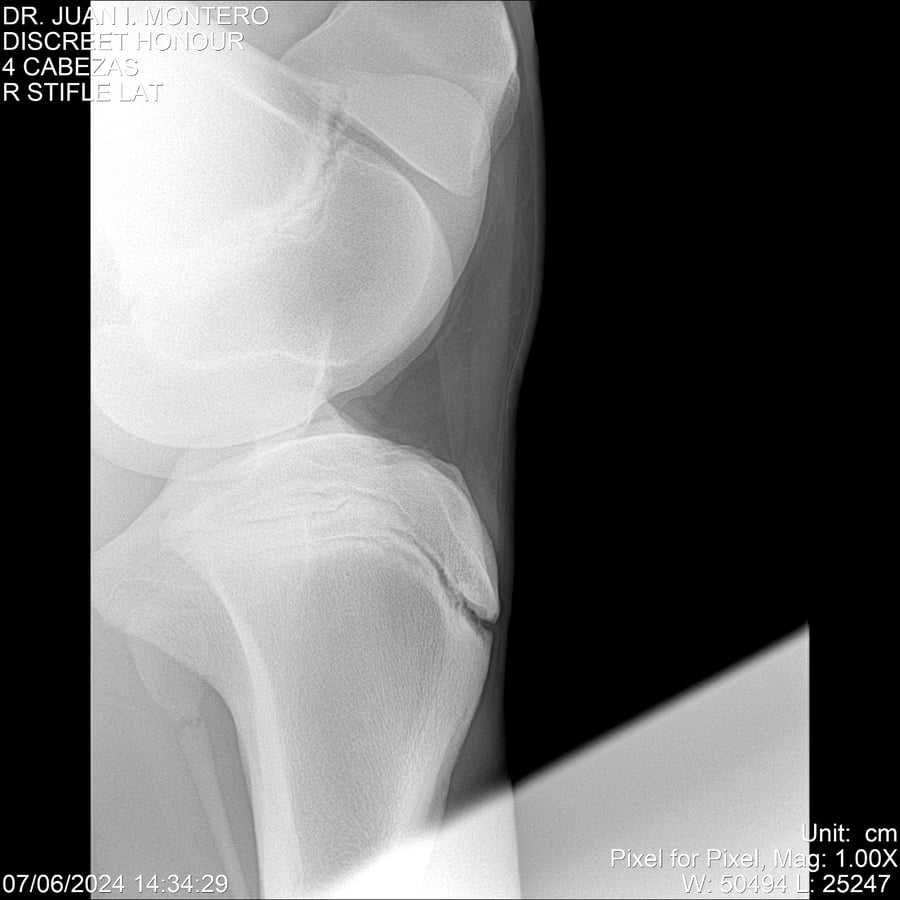

LOTE 6, DISCREET HONOUR 🔥 🔥 🔥 Lote Anterior Volver al remate Lote Siguiente Ficha Contacto Montevideo - Ficha del Lote Identificador: #281093 Categoría: Yeguarizos Montevideo - 82 Visualizaciones ClicData Contacto Empresa: Abelenda N. R., Walter Hugo Nombre*: Teléfono* : E-mail* : Mensaje Enviar Registrese gratis Este contenido Exclusivo está disponible sólo para usuarios registrados Ingresar